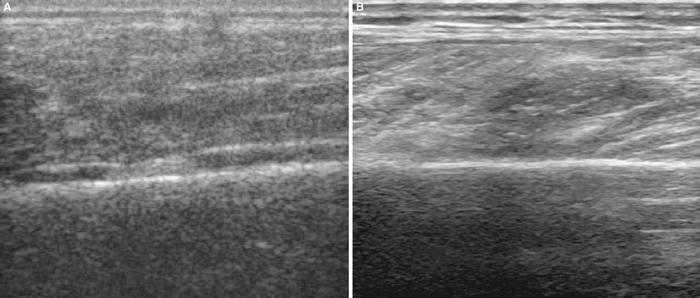

Tendinosis rotuliana

Este paciente refería dolor relacionado con el esfuerzo durante el ejercicio de carrera y salto desde hacía 3 semanas. Con el equipo E-A se observa una mínima predominancia hipoecoica en la unión hueso-tendón (fig. 3A); sin embargo, con el equipo E-B y ampliando la imagen se aprecia un claro predominio hipoecoico, lo que permite confirmar el diagnóstico de tendinosis degenerativa (fig. 3B)29,30.

Figura 3 A) La observación en corte longitudinal permite con el equipo E-A observar una zona hipoecoica de pequeño tamaño en la unión del tendón rotuliano al polo inferior de la rótula. B) En el mismo corte con el equipo E-B la zona hipoecoica afecta a los dos tercios superiores del tendón rotuliano.

Pero la aplicación de visión panorámica del equipo E-B nos permite precisar la amplitud de la lesión, confirmando que ésta ocupa los dos tercios proximales del tendón rotuliano (fig. 4).

Figura 4 La zona hipoecoica queda ampliamente delimitada en los dos tercios superiores del tendón rotuliano utilizando el equipo E-B en un corte longitudinal panorámico.